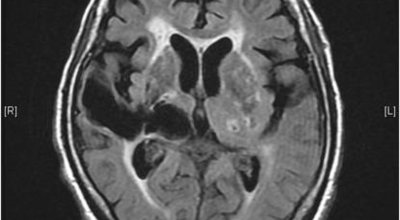

뇌경색의 주된 원인은 혈전입니다. 혈전이란 혈관 속에 피가 굳어진 덩어리를 얘기하는데 이것이 혈관을 막는 것이 뇌경색에 큰 영향을 준다고 해요. 평균적으로 많이 나타나는 연령대는 5~60대입니다. 뇌경색은 양쪽 뇌에 모두 생기는 것이 아니라 주로 한쪽 뇌에만 발생하지만, 주로 한쪽 팔다리가 마비되거나 얼굴 근육이 굳어버리기도 해요.

뇌경색이 생기는 원인은 아주 다양해요. 뇌경색은 뇌의 혈관이 막혀 뇌의 일부가 죽는 질병을 말하는데 주로 뇌경색의 원인은 혈전이며, 혈전으로 인해 뇌혈관이 막히는 위험 인자는 혈전을 발생하게 해요. 또한 동맥경화나 심장병, 혈관박리, 뇌혈관 기형 등으로 말미암아 생기게 될 수 있다고 하며 대부분이 60세 이상의 고령층에서 빈번히 나타나는 질환으로 알려져 있답니다.

특히 당뇨병이나 고혈압, 고지혈증 등을 앓고 있는 경우 함께 증상이 동반될 수 있는데요 그 중에서도 가장 큰 원인은 고혈압으로 볼수 있으므로 주로 겨울철 노인에게 잘 발생해요. 뇌경색은 뇌의 한쪽에서 발생하는 경우가 많다고 하며 한쪽 팔다리가 마비되는 것이 전형적인 증상이라고 볼 수 있어요.